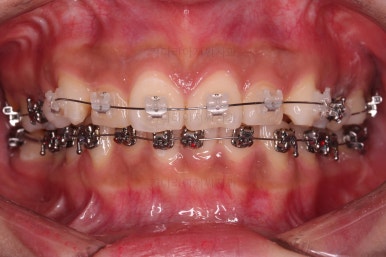

3. 치료경과

장치를 부착했고요.

이번에 환자분이 선택한 장치는 윗니는 자가결찰 세라믹, 아랫니는 자가결찰 메탈이었습니다.

이렇게 혼용해서 사용해도 되는 조합들이 있고요.

이번 환자분은 웃을 때 이가 많이 보이는 타입이 아니셔서 아랫니는 좀 더 튼튼하고 저렴하기까지한 메탈장치를 선택하셨죠.

장치 부착 느낌과 장치를 부착한 직후의 입이 튀어나오는 정도를 참고해 주시고요.